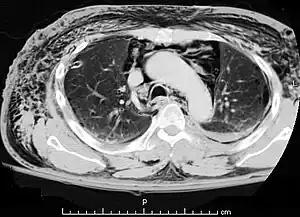

| A CT scan showing air in the mediastinum | |